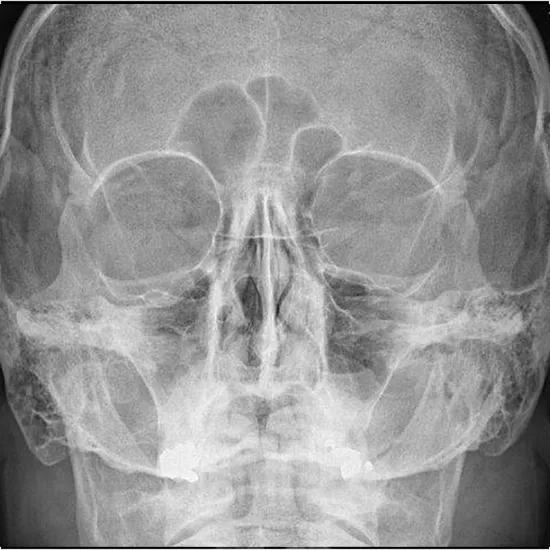

The region of the eye sockets, nasal bridge, and cheekbones may all be seen using an X-ray of the orbit AP and Lateral Views. Eye sockets are made up of a ring of thin bones that enclose the eye.

• To inspect the area surrounding the eye sockets for any fractures in the bone.

• To rule out the possibility that there are foreign bodies present in the eye that cannot be seen with conventional ophthalmic equipment.